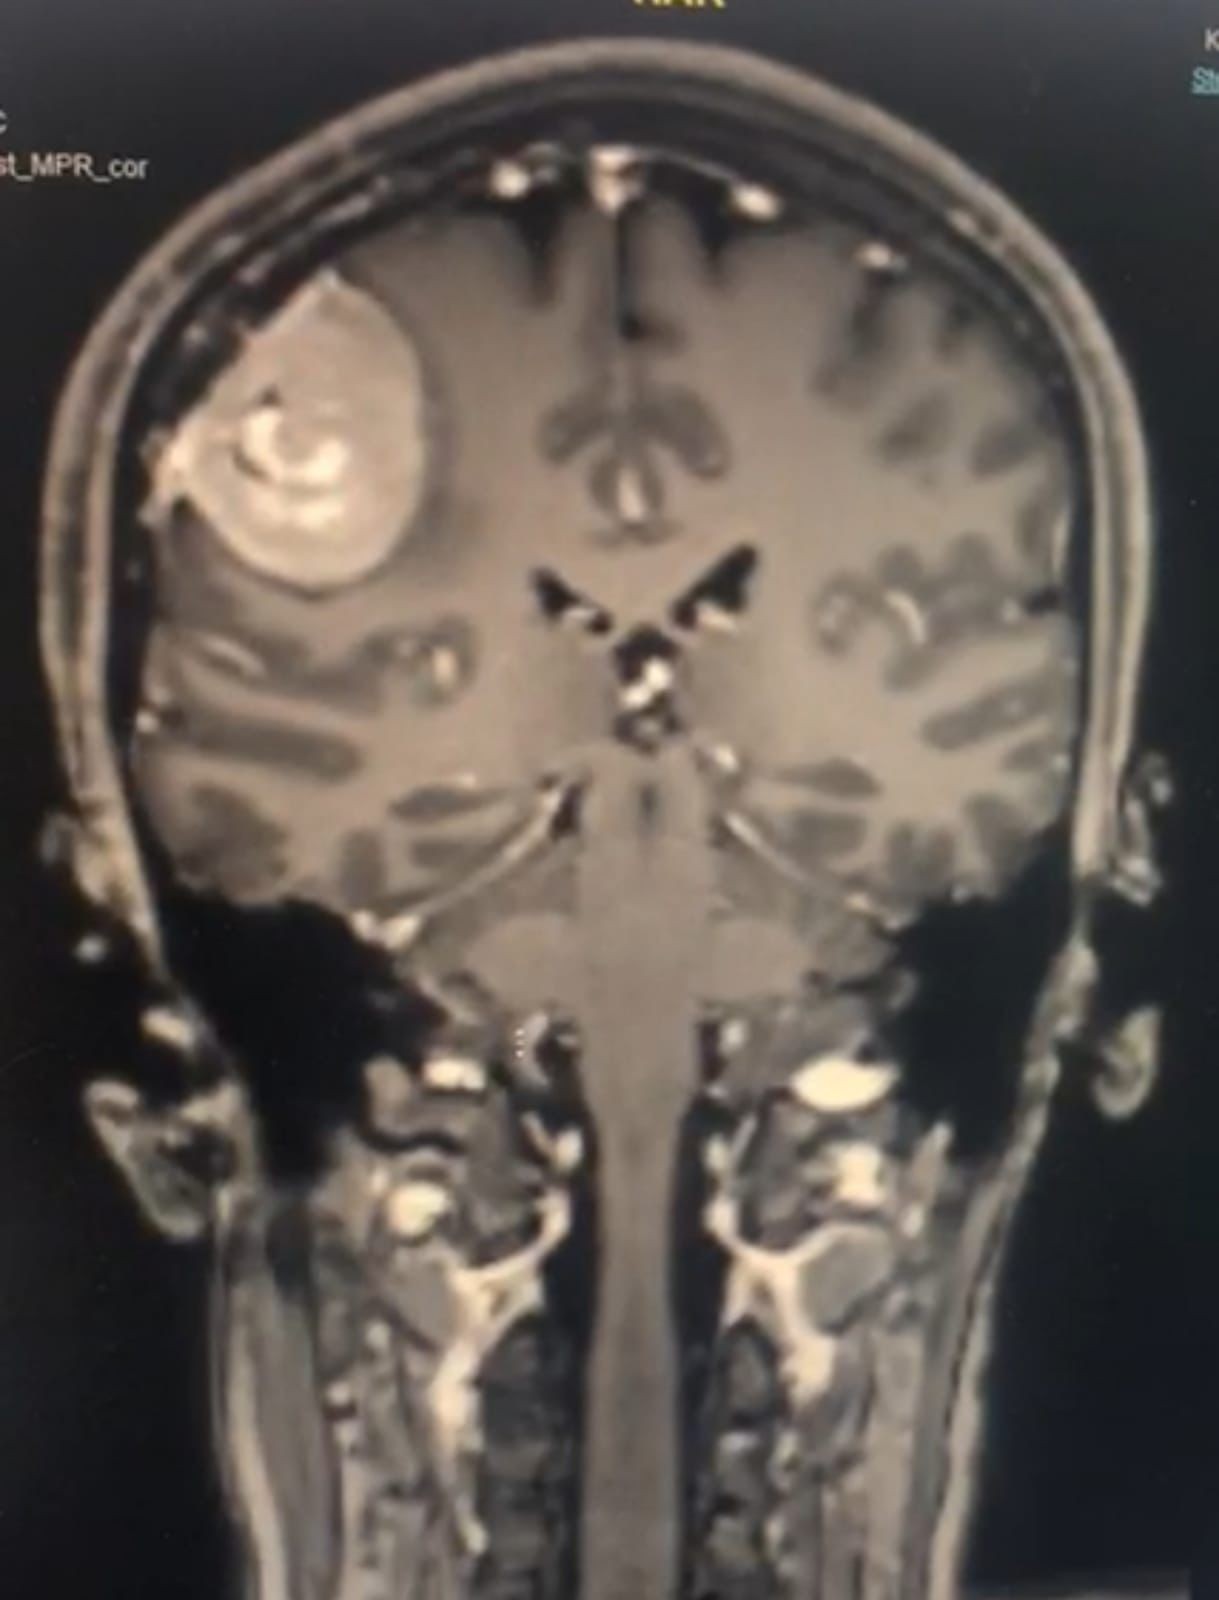

وبدأت القصة بوصول السيدة إلى العيادة المتخصصة، وهي تعاني من صداع عنيف منذ أكثر من عامين، وبإجراءات الفحوصات اللازمة ,اكتشف أن لديها "ورم سحائي في الفص الجداري ",سبب ضغطا على "الدماغ".وقرر الفريق إجراء عملية جراحية دقيقة ,تم من خلالها استئصال الورم بنجاح تام, وعادت السيدة إلى ممارسة حياتها الطبيعية بعيدا عن الصداع المزمن.